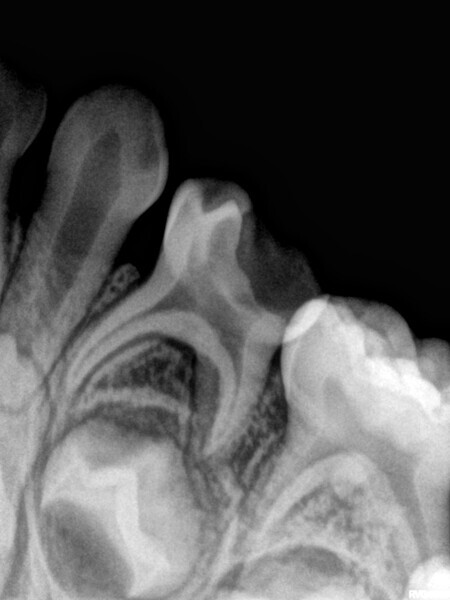

Cas 1 (Figs 1-4)

Cette patiente âgée de 4 ans et 7 mois présentait une douleur qui affectait la seconde molaire temporaire inférieure droite depuis plusieurs jours. L’examen clinique a révélé un gonflement du versant vestibulaire de la gencive et un œdème facial, ainsi qu’une carie occlusale profonde.Un diagnostic de nécrose pulpaire et d’abcès apical symptomatique ayant été posé, un traitement a été prescrit à la patiente, afin de maîtriser l’infection aiguë, et un nouveau rendez-vous a été fixé après l’antibiothérapie. Lors du deuxième rendez-vous, elle ne présentait plus aucune douleur et l’abcès buccal s’était partiellement résorbé. Il a été décidé de procéder à une pulpectomie et à la restauration de la dent. Dans ce cas, la dent présentait une extrusion excessive de matériau d’obturation. Après 15 mois, la réévaluation a confirmé l’absence de signes cliniques ou radiologiques pathologiques, et une apposition osseuse était visible dans la zone de la furcation.